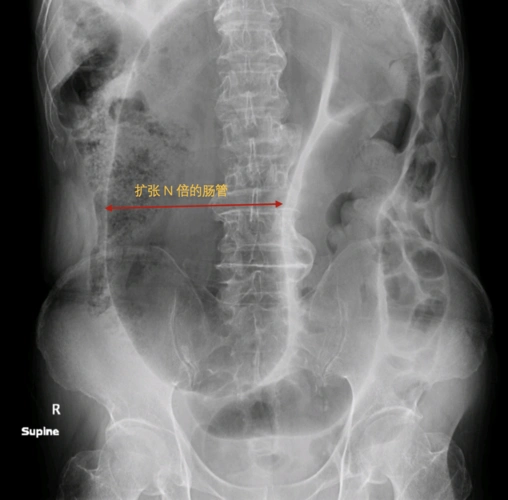

肠扭转的超声诊断

小肠扭转影像学表现医学影像图